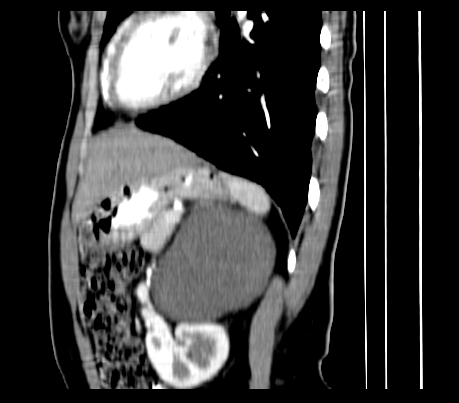

腹部平扫